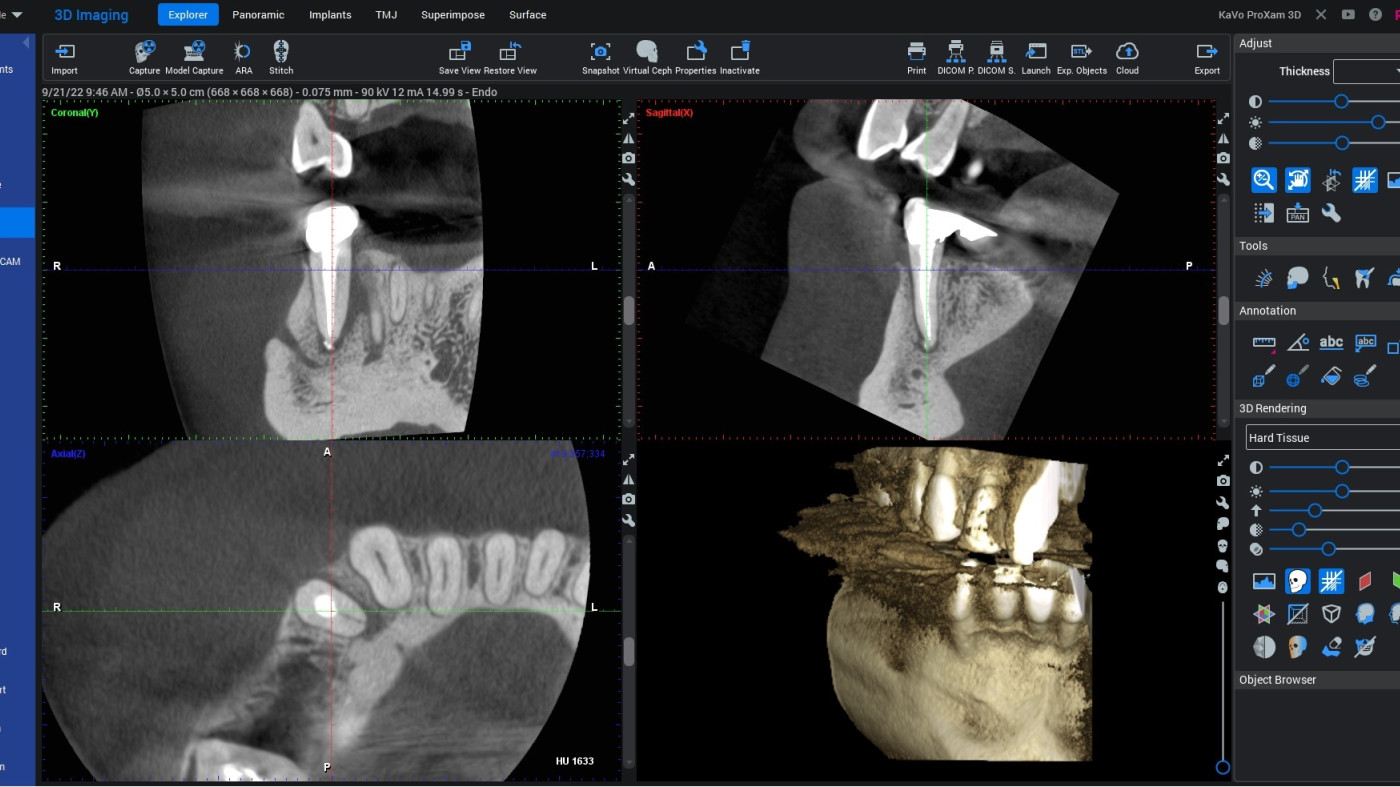

Webinar poświęcony jest praktycznemu wykorzystaniu oprogramowania Romexis w codziennej pracy z badaniami CBCT. Uczestnicy krok po kroku nauczą się, jak prawidłowo otwierać, konfigurować i analizować dane obrazowe, aby uzyskać maksymalną wartość diagnostyczną i uniknąć najczęstszych błędów interpretacyjnych.

• poprawne otwieranie i wczytywanie badań CBCT w programie Romexis

• orientacja w interfejsie i ustawieniach obrazu (okna, kontrast, przekroje)

• zasady prawidłowej interpretacji przekrojów osiowych, strzałkowych i czołowych

• najczęstsze artefakty i pułapki diagnostyczne w CBCT

• praktyczne wskazówki ułatwiające analizę badań w planowaniu leczenia

Możliwości oraz ograniczenia obrazowania 2D i 3D – kiedy i jakie badanie należy zlecić pamiętając o zasadzie ALARA. Jakość badania RTG – co na nią wpływa, jak ją oceniać, jak wyeliminować potencjalne błędy rzutujące na obniżenie jakości badań radiologicznych. Poruszanie się po badaniu CBCT – możliwości oceny tkanek oraz stanów patologicznych poprzez wyświetlanie badania w formie przekroi, rekonstrukcji wolumetrycznej, rekonstrukcji badań 2D (MPR – multi planar reconstruction). Mnogość narzędzi w oprogramowaniu KaVo RTG – jak efektywnie wykorzystywać je na co dzień w poszczególnych przypadkach z zakresu chirurgii, endodoncji, ortodoncji, etc.

• poruszania się po oprogramowaniu dedykowanemu 3D.